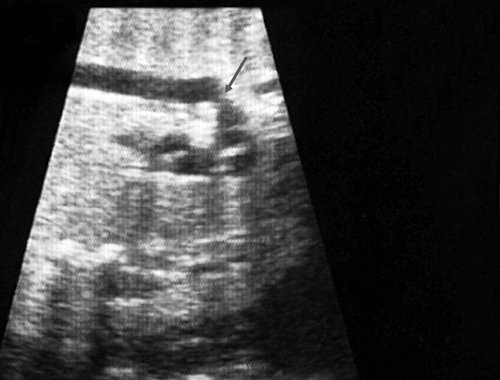

Согласно "теории дуктальной ткани" коарктация аорты возникает в результате миграции гладких мышечных клеток протока в предуктальную аорту, с последующей констрикцией и сужением просвета аорты [4]. При формировании коарктации аорты в области перешейка сохраняется сужение различной протяженности и формы (рис. 2, 3). Наиболее часто это проявляется в виде локальной перетяжки, выше или ниже которой диаметр аорты сохраняется в норме.

Рис. 2. Ультразвуковое исследование восходящего отдела, дуги и нисходящего отдела аорты. Стрелкой указано место сужения.

Рис. 3. Трехмерное изображение сердца и аорты плода в 16 нед беременности. Стрелкой указано место сужения аорты. AO DESC - нисходящий отдел аорты, COR - сердце.

Известно, что диагноз данного порока сердца опирается на прямой признак - визуализацию места сужения аорты, и, возможно, расширение проксимального отдела аорты. Однако четко визуализировать участок сужения аорты у плода достаточно трудно и удается только в единичных наблюдениях. Порок можно увидеть лишь тогда, когда имеется уменьшение диаметра перешейка аорты более чем на 1/3 по сравнению с нормой для каждого срока беременности (см. рис. 2, 3).